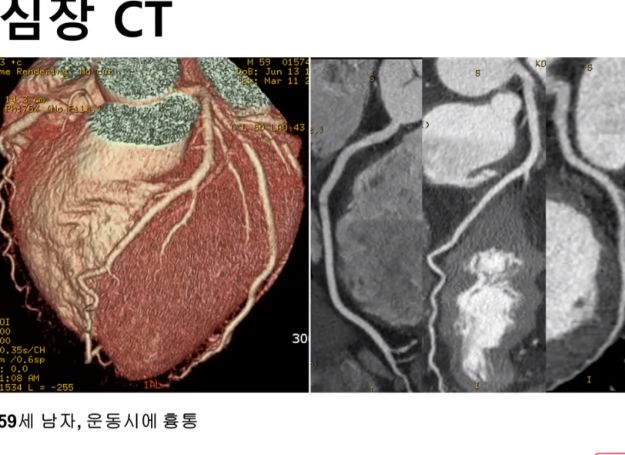

협심증, 심근경색증(박덕우교수/서울아산병원 심장내과, 2019년): 100세시대에 아주 중요한 것이 혈관건강 본문

여기서 더 의심되면 심장핵의학검사, 심장CT검사를 한다.

마지막 확진방법이, 필요하면 관상동맥조영술1

- 시술이다. 실시간으로 엑스레이 영상을 찍어보면서 의심가는 관상동맥입구(여기까지는 다리 혈관을 찔러 가는 관을 심장까지 보낸다)에서 조영제를 흘리면, 관상동맥이 막힌 데까지만 조영제가 흘러들어가는 게 엑스레이로 보인다. [본문으로]